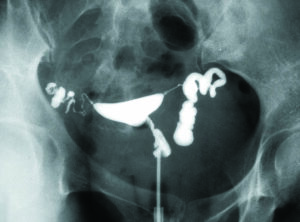

卵管水腫・子宮内膜症:移植の成否を左右する大きな因子です。クラミジアの治療歴がある、帯下(おりもの)が多い(シート常用)、月経痛が強い、嚢腫・筋腫・子宮外妊娠などの手術歴があるなどの場合には、子宮卵管造影やMRIを行い、着床障害・不育症の原因になる卵管水腫・卵管癒着・子宮内膜症などがあれば腹腔鏡検査を行います。

腹腔鏡検査・子宮鏡検査と手術:不妊原因がわからない場合、排卵があってヒューナーテストが正常な場合、何回移植しても妊娠しない場合(反復着床不全)、妊娠しても流産してしまう(反復流産)などの場合には、卵管水腫や卵管周囲癒着などを合併している可能性が高く、腹腔鏡検査や子宮鏡検査が必要となります。

腹腔鏡検査によって異常を認めた場合には、同時に腹腔鏡下手術(卵管開口術、癒着剥離術、子宮内膜症除去術など)を行い、不妊原因をとり除くとともに子宮内の着床環境を正常にとり戻します。

卵管水腫の子宮卵管造影所見